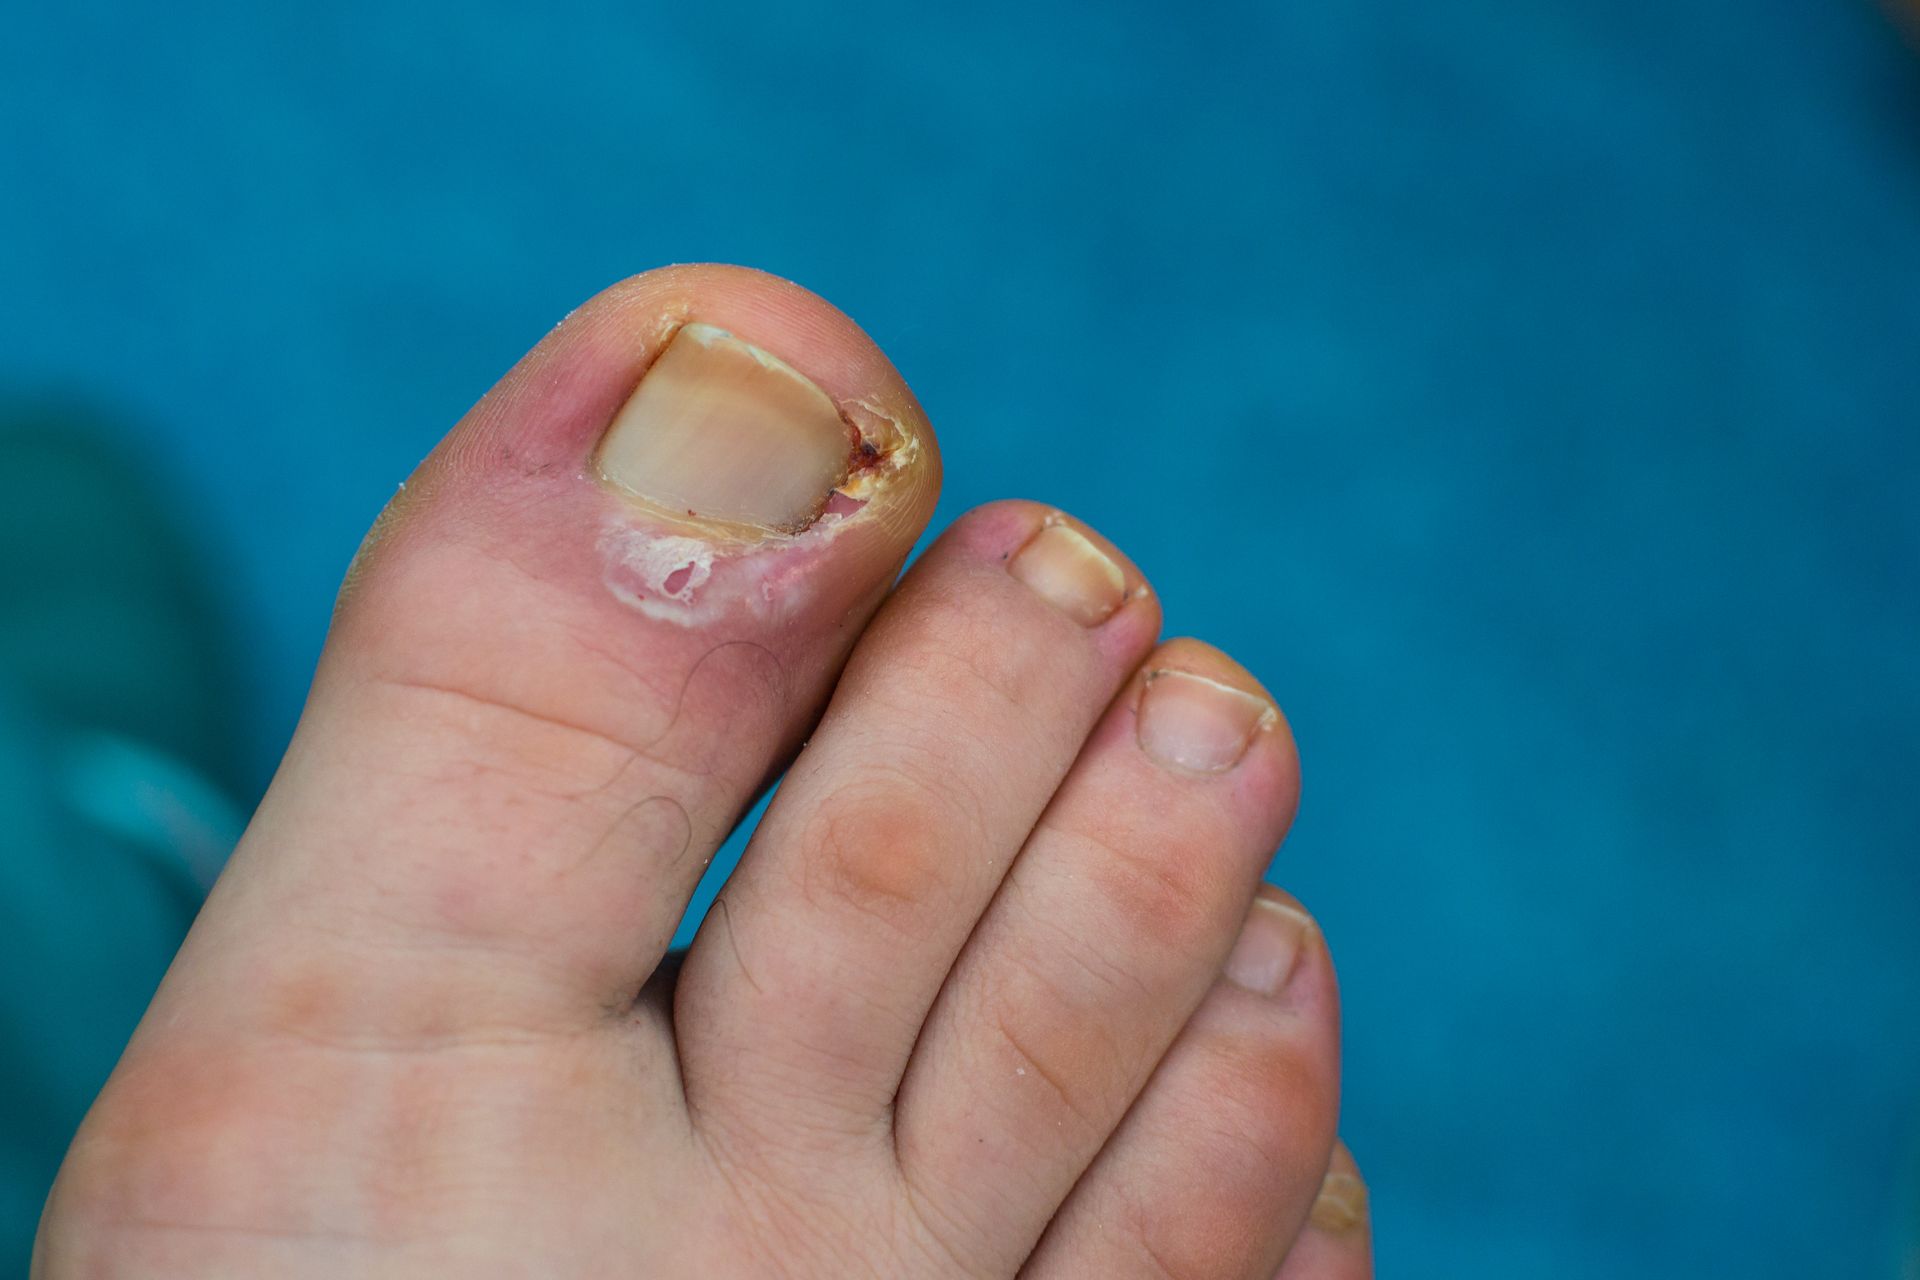

Podiatric medicine focuses on the diagnosis and treatment of conditions affecting the foot, ankle, and lower leg. Podiatrists use proven, hands-on approaches to evaluate symptoms, identify the source of pain, and provide effective treatment options. Care may include preventive services, custom orthotics, therapeutic treatments, medications, and surgical solutions when needed, all aimed at improving comfort, mobility, and overall foot health.